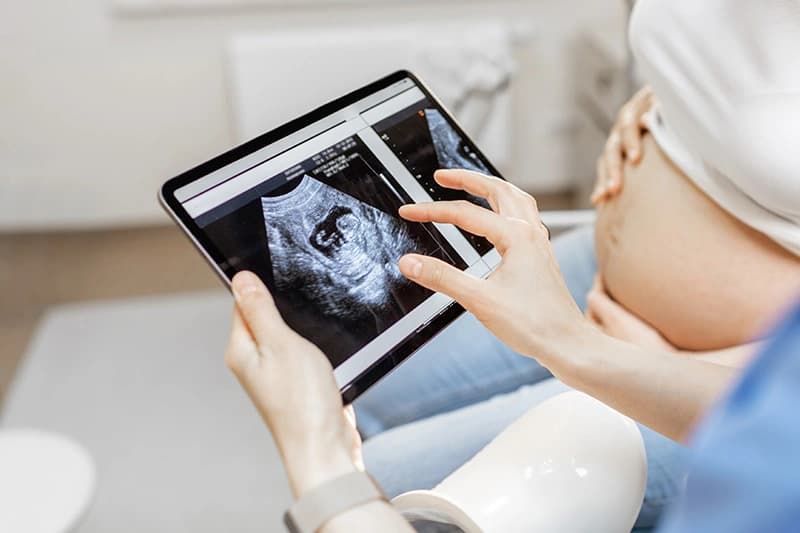

Anomaly Scan / Anatomy Scan: What should you expect?

Heba Alkutbi · February 8, 2024

Pregnancy is a journey filled with moments of joy and anticipation, and the anomaly scan—or anatomy scan—is a significant and exciting milestone. This article will guide you through what an anomaly scan is, what to expect during the procedure, the findings you might encounter, and how to interpret the results.